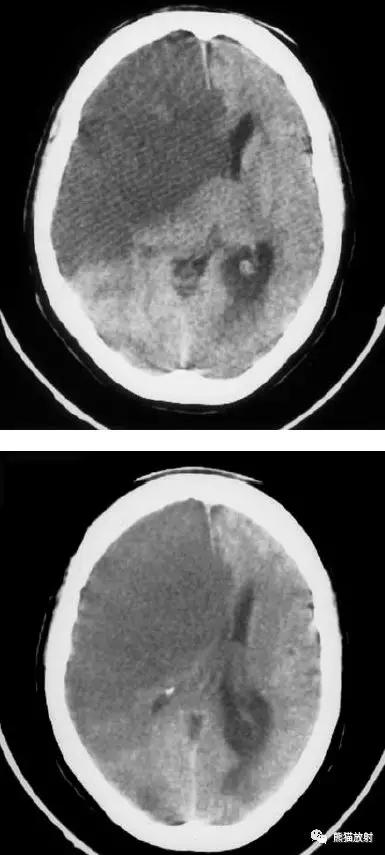

右侧豆状核梗死灶(发病后15d),明显均匀强化。另左侧丘脑见腔隙性梗死灶。

左侧大脑中动脉区域大面积梗死,明显不均质强化。